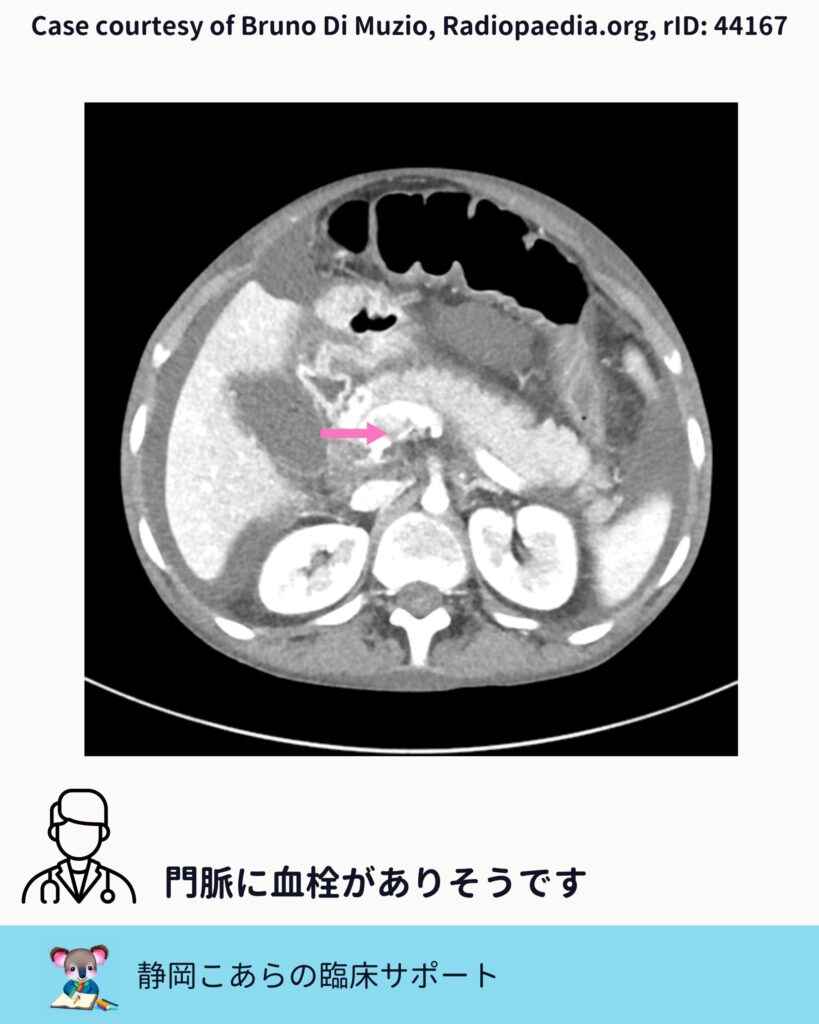

門脈血栓をどう見るか

今回の症例では、門脈内に造影欠損が認められます。スライスを追うと、はっきりとした血栓として確認できます。

門脈血栓症では、 ・門脈の拡張 ・造影欠損 ・側副血行路の有無

こうした点をセットで評価していくことが、臨床的には自然です。